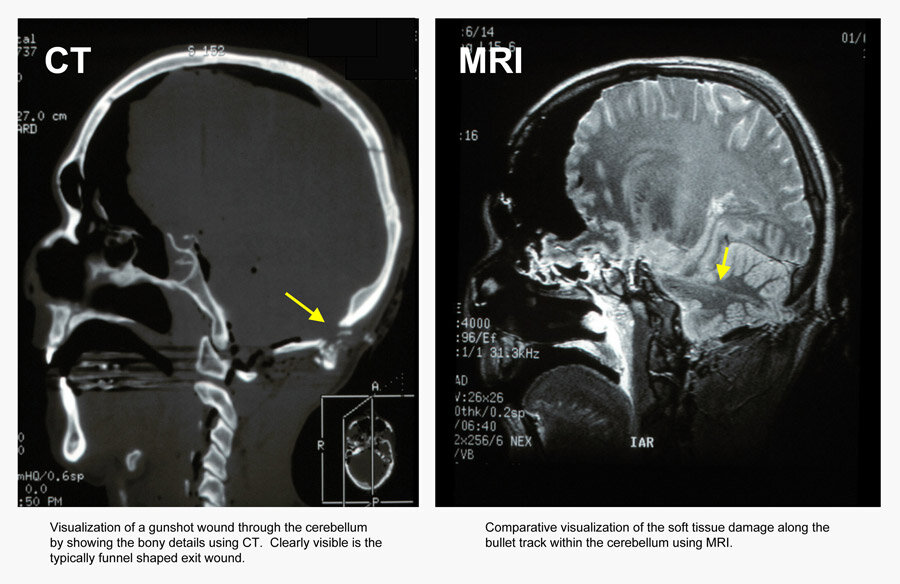

Virtual autopsies are starting to be used as a precursor to the physical kind. The Pentagon has already used this technology on the remains of soldiers who died in Iraq and Afghanistan to determine the effectiveness of helmets and body armor for protection. Forensic investigators in Sweden and Switzerland have performed numerous virtual autopsies on murder victims and are working to perfect the technique. Medical examiners from all over the world, including the U.S. have taken interest.The benefit of using CT and MRI to create full-body scans of the deceased is that it is non-invasive. Full-body 3D images generated from the scans can be easily be manipulated by zooming in, cropping, and rotating in any direction, something not possible by physical autopsy. In murder victims, bullet paths can instantly be found and the extent of knife wounds easily visualized. This would normally take hours through physical autopsy.